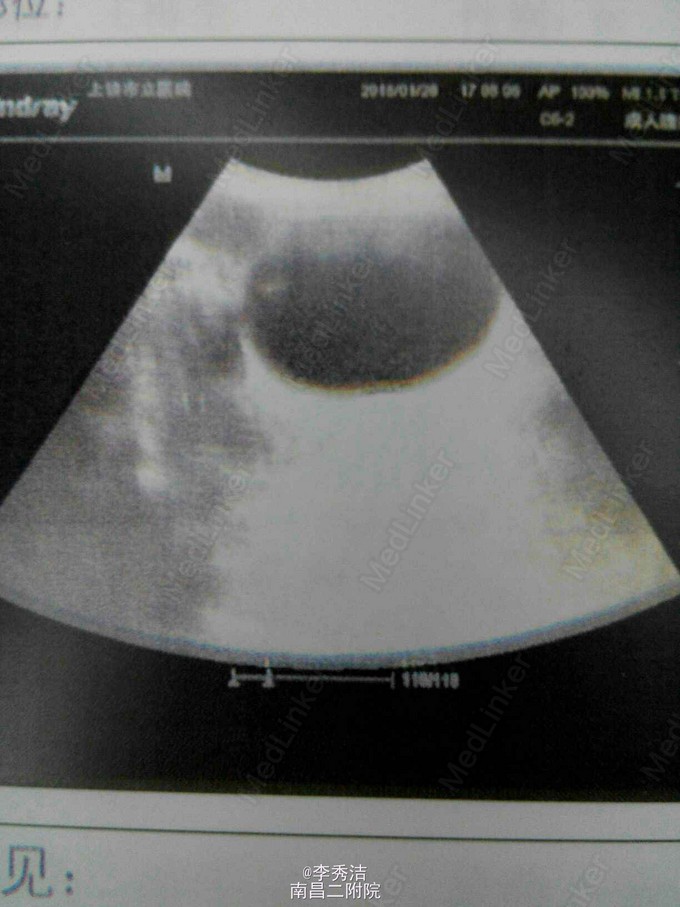

患者女,55岁,一周前体检发现宫颈癌,无任何自觉症状。诊断性刮宫病理结果示:子宫颈中分化浸润性磷状细胞癌。给予全子宫+双附件切除加盆腔淋巴结清扫,后期予顺铂+紫杉醇化疗。